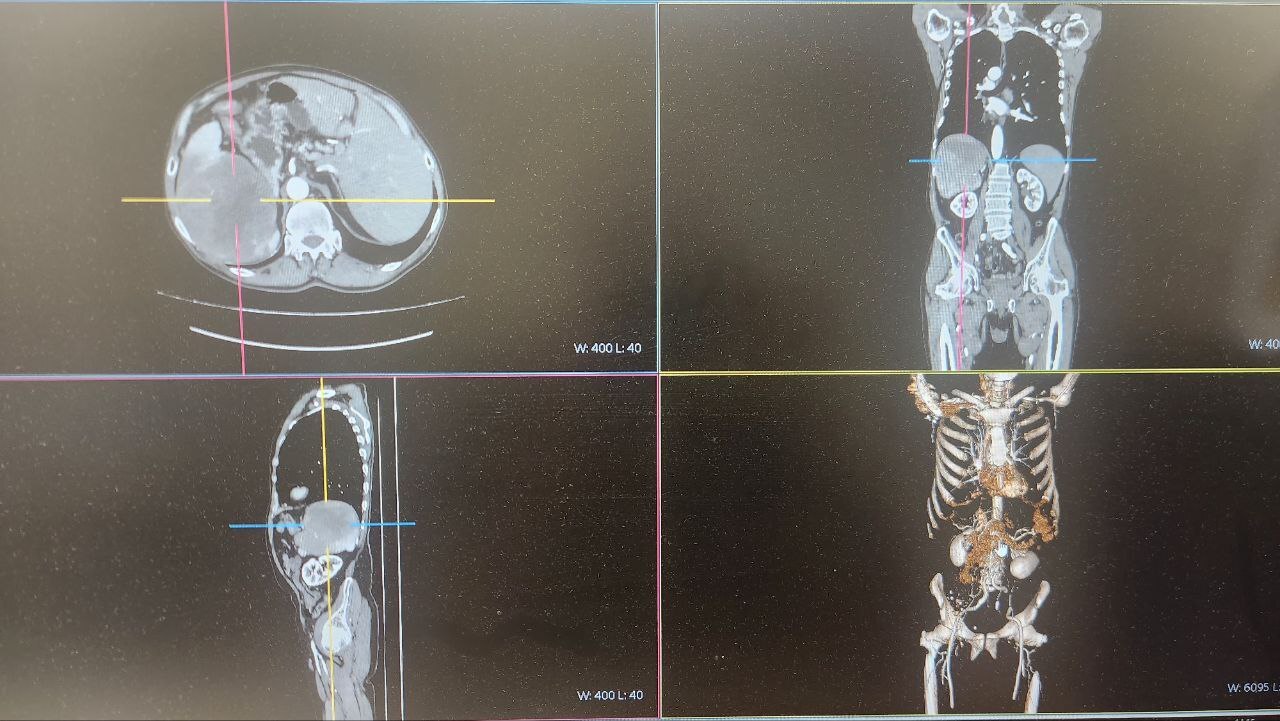

Опухоль нашли у 69-летнего туляка на плановом УЗИ брюшной полости. Дальнейшее обследование подтвердило диагноз: опухоль поразила селезенку, лимфоузлы и хвост поджелудочной железы.

Врачи приняли решение об удалении единым блоком селезенки, части поджелудочной железы с опухолью и пораженными лимфоузлами с использованием лапароскопического метода.